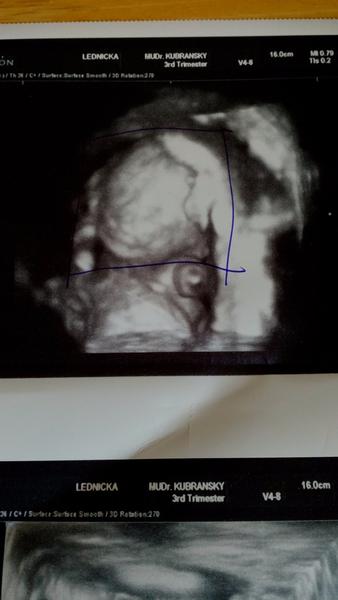

Dnes som bola na sono a malé si zakrývalo tváričku oboma ručičkami, nechcelo vidieť doktora 🙂 pýtala som sa na pohlavie, nebol si istý, že vraj je to dievčatko. 🙂